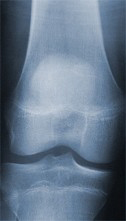

Röntgenaufnahme eines gesunden Kniegelenkes

Der Gelenkspalt entspricht einem gesunden Knie ohne Abnutzungserscheinungen des Gelenkknorpels.